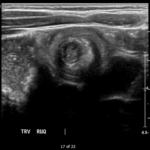

The patient’s abdominal ultrasound revealed intussusception in the right upper abdominal quadrant. The transverse ultrasound view showed a “doughnut sign” (dashed yellow line), telescoping bowel (yellow arrow), and invaginated hyperechoic mesenteric fat with crescent configuration (dashed orange line). The sagittal ultrasound view demonstrated the intussusception formed by the outer recipient bowel loop (yellow arrows), invaginated hyperechoic mesenteric fat (orange asterisks), and telescoping bowel centrally (red arrow).

Ultrasonography should be the initial imaging modality in cases with clinical suspicion for intussusception.4 Previously, contrast enemas were often used as a diagnostic tool and treatment modality. Studies have demonstrated that the modality choice had been related to age, with infants less than six months more likely to undergo enema while children greater than four were more likely to have a computed tomography scan or ultrasound.5 In the pediatric population, ultrasound has a sensitivity of 97.9% and specificity of 97.8% for diagnosis of ileocolic intussusception.6 A “doughnut,” “pseudokidney,” or “target sign” are diagnostic findings.3,7 The study could be performed by radiology or at the bedside in the ED.8,9 A study reported that with limited training, ED physicians could accurately perform ultrasound to diagnose intussusception, with a sensitivity of 85% and a specificity of 97%. Further studies are needed to determine the utility of bedside ultrasound for the diagnosis of intussusception in the community setting.3